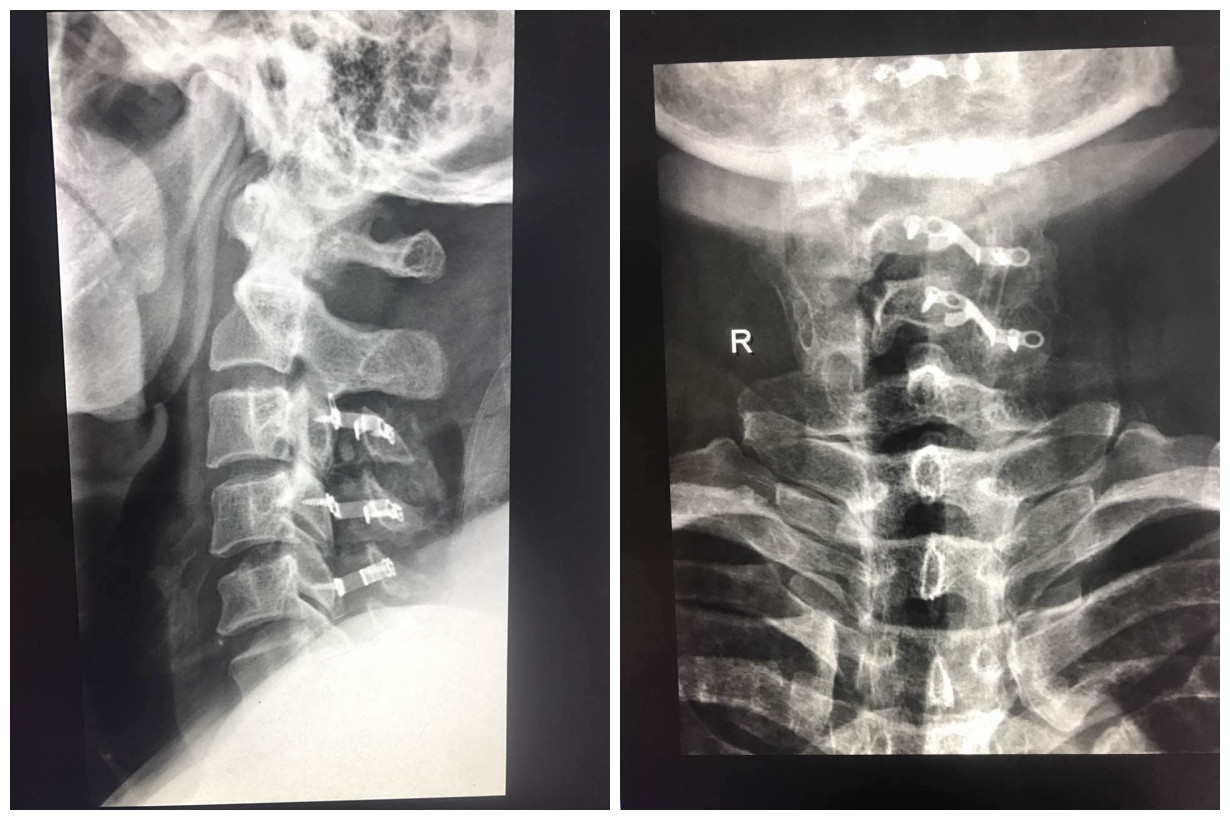

患者付某,男,52岁,因双下肢麻木、无力伴走路不稳半年,前往各大医院就诊,长时间保守治疗均效果不佳且症状逐渐加重,后出现双手麻木4个月,为求进一步诊治,遂来我院骨二科就诊。入院行颈椎CT及MRI检查示:多节段椎管狭窄并后纵韧带骨化,颈髓受压变性,并伴有原发性颈椎管狭窄症。入院诊断为:1.颈椎管狭窄症2.颈椎后纵韧带骨化颈脊髓变性。入院后,科主任卜祥鹏迅速组织科室技术骨干展开讨论,详细讨论患者病情,并征得患者同意,决定为其行颈后路椎管减压术。恰逢我院磨钻系统配备到位,卜主任充分完善术前准备,联系齐鲁医院教授、磨钻系统厂家,商讨手术方案,限期于全麻下行颈后路单开门椎管减压U型钛板内固定术。该手术由齐鲁医院教授及李秀春副主任医师,常乐主治医师联合完成,磨钻系统发挥了其重大作用,术中开门1.5cm并有效维持,硬脊膜漂浮好,手术时间明显缩短,术后患者恢复良好。

颈后路单开门手术可以充分保留棘突韧带附着,减轻术后轴性症状,有效降低门轴断裂几率,减少手术时间,而U型钛板于近年被广泛应用于临床,被公认为有效维持开门的良好内固定物。